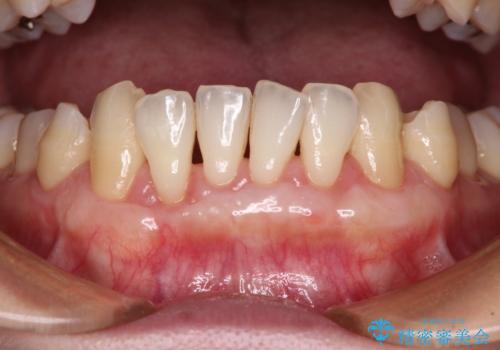

年々下がる歯茎を何とかしたい 歯肉移植術による根面被覆

担当医 藤巻太一朗